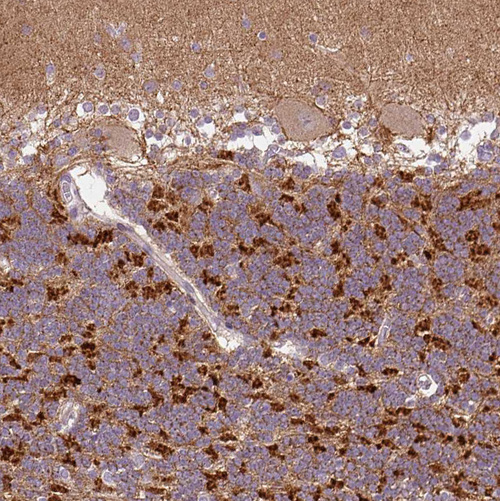

Immunohistochemical staining of human skeletal muscle shows strong cytoplasmic positivity in myocytes.